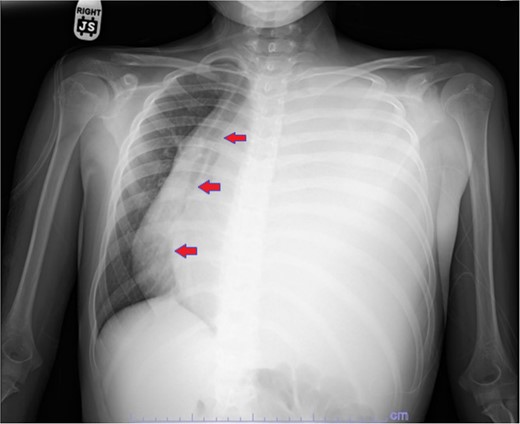

Our patient is a 10-year-old Caucasian female with a history of early adrenarche, ADHD, and COVID-19 and no past surgical history. She presented to the ED with a month-long history of persistent coughing, shortness of breath on exertion and speaking, and left-sided chest pain that began after a diagnosis of mildly symptomatic COVID-19. A physical exam revealed decreased breath sounds on the left, with a left-sided chest protrusion. A plain film and CT demonstrated a normal right lung, with a significant mediastinal shift toward the right, displacement of the heart into the right hemithorax, with complete whiteout of the left hemithorax, and demonstrating a mix of solid and cystic foci, with a round opacification at the left lung base (Figs 1 and 2). The patient underwent an uncomplicated left thoracotomy with excision of two masses, one being 22.5 × 21.0 × 10.5 cm and the other being 13.5 × 11.5 × 6.2 cm. These masses weighed 2394 g in aggregate. The specimens consisted of well-encapsulated tumors attached to the posterior aspect of the chest wall. A regional, positive lymph node measuring 3.0 × 2.2 × 1.0 cm was also resected. Due to the large size of the tumor and the requirement for clean margins, parts of the latissimus dorsi and serratus anterior muscles were also resected. By postoperative day (POD) 0, the left lung had already filled the left hemithorax, and the mediastinal shift had corrected (Fig. 3). The chest tube was removed on POD 5, and a plain film showed continued expansion of the lung to full size and resolving pulmonary edema and atelectasis (Fig. 4). The patient was discharged home on POD 5. The tumor staging was T4N1M0. The tumor was positive for vimentin, CD56, synaptophysin, chromogranin, and NSE. The tumor was negative for pancytokeratin, Cam5.2, EMA, S100, desmin, SMA, SOX10, HMB45, CD117, DOG1, CD99, PR, CD68, WT1, CD30, p53, Alk1, GFAP, and nuclear β-catenin. Next-generation sequencing showed an MGA:NUTM1 fusion, supporting a final diagnosis of high-grade MGA:NUTM1 fusion SCS. Given the size and grading of the tumor, the patient underwent adjuvant CT-RT with ifosfamide, doxorubicin, and proton beam radiotherapy, with supportive doses of MESNA and dexrazoxane for 4.5 months post-operatively. The basis of this treatment is ARST0332 Arm C [6]. Before treatment initiation, the patient underwent an uncomplicated left oophorectomy for reproductive cryopreservation. A PET/CT prior to CT-RT showed hypermetabolic activity in several areas. These included the pleural resection margin, a mediastinal lymph node concerning for metastasis versus postsurgical change, and a left axillary lymph node concerning for metastatic disease. During treatment, the patient contracted human metapneumovirus and rhino/enterovirus, resulting in febrile neutropenia. The patient was successfully treated with blood and platelet transfusions and pegfilgrastim. Upon completion of CT-RT, PET/CT imaging showed no evidence of residual disease, with minimal focal hypermetabolic activity as compared to the previous imaging (Fig. 5).

Plain film showing complete left hemithorax opacification and mediastinal shift (arrows) to right.